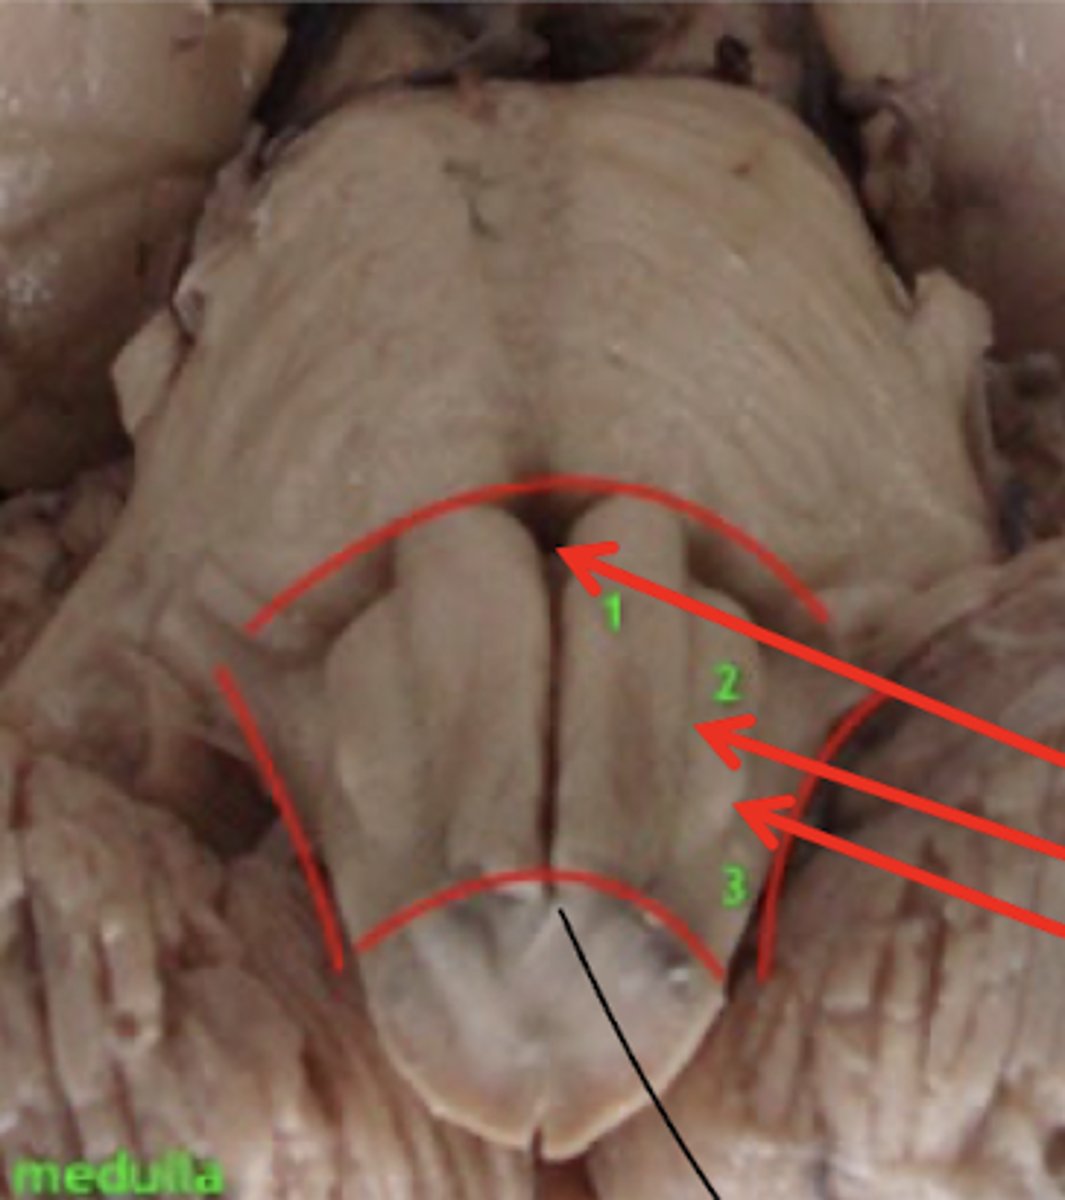

What are the structures of the ventral medulla oblongata (medial to lateral)?

1. pyramid

2. olive

3. lateral funiculus

What divides the right and left pyramid of the medulla oblongata?

anterior median fissure

What divides the pyramid from the olive of the medulla oblongata?

anterior lateral sulcus

What divides the olive and lateral funiculus?

posterolateral sulcus

Do the pyramids run the entire length of the medulla oblongata?

yes

Does the olive (right and left) run the entire length of the medulla oblongata?

no -- only half (cranial)

Where does the 4th ventricle end?

medulla

cranial medulla -- "open" half

caudal medulla -- "closed" half

What cranial nerves reside in the medulla?

1. CN IX

2. CN X

3. CN XI

4. CN XII

Where do CN IX, X, and XI exit the medulla oblongata?

exit the dorsolateral sulcus (

posterolateral sulcus)

3rd sulcus (counting medial to lateral) -- most lateral

Where does CN XII exit the medulla oblongata?

anterolateral sulcus -- as numerous roots

2nd sulcus (counting medial to lateral)